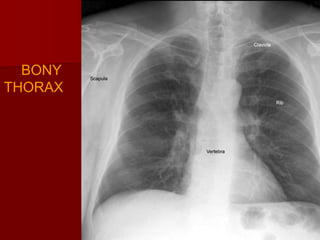

Bony thorax

Chest x-ray primarily visualizes intrathoracic

structure but also outline the shoulder girdle

,ribs, cervical and thoracic vertebrae.

Sternum is often well outlined .

Shape of the thorax varies with age and body

habitus.

Angulations of the ribs varies with body types.

downward angulations: minimal in short

hypersthenic individual. And maximal in

asthenic patient.